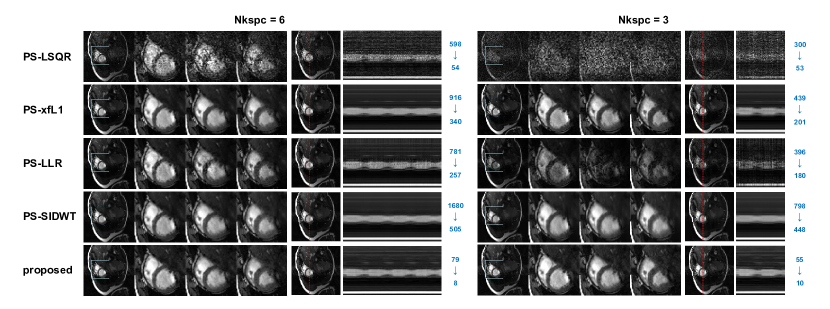

The reconstructed images for different Nkspc settings are shown in Figure 4. Under Nkspc=18, all the models produce similarly high quality images, with nRMSE slightly above 0.01, PSNR above 38 and SSIM above 0.90. When Nkspc is reduced to 9 and 6, the image quality of PS-LSQR model deteriorates obviously, while the performance of the other algorithms are only slightly affected. When the Nkspc is further reduced to 3, a notable image quality decline can be observed for the PS-xfL1, PS-LLR and PS-SIDWT methods. Only the proposed method can still keep good visual image quality. This suggests that the proposed method is the most stable algorithm when the acquisition time is significantly shortened. Besides, it can be observed that the operator optimization significantly reduces the computation time for all algorithms. The acceleration factor increases with the Nkspc value, which means more reconstruction time can be saved if the acquisition time is prolonged. For all Nkspc settings, the proposed method is always the fastest algorithm.

The reconstructed images of one data case using the best are displayed in Figure 7. Obviously, when Nkspc is reduced from 6 to 3, the reconstruction error deteriorates significantly. The images reconstructed by PS-LSQR model is totally corrupted by noise. The images reconstructed by PS-LLR model suffer from dark streaking artifacts on the M-mode motion profile, which implies that the image quality fluctuates from frame to frame. The image reconstructed by PS-xfL1 model displays better image quality, but residual dark streaks can still be observed from the M-mode images. The image reconstructed by PS-SIDWT model displays severe smoothing effects on the M-mode images, where the atrium motion profile is blurred. Scattered noise can be perceived on the images reconstructed by PS-xfL1 and PS-SIDWT method. In comparison, the proposed method produces the best visual image quality and the clearest motion profile. Obviously the reconstruction error level of the proposed method is the lowest among all the models, and the error distribution is also more uniform across the image.

The reconstructed images of one volunteer are shown in Figure 8. The results are consistent with the retrospective experiment, with only slight differences. Under Nkspc=18, all the regularized PS model algorithms have similarly good image quality. However, the image reconstructed by PS-LSQR method is obviously worse than other methods. When Nkspc is further reduced to 9 and 6, the performance of PS-LSQR deteriorates very quickly, while other methods can still maintain relatively good image quality. When Nkspc is reduced to 3, the images reconstructed by PS-LSQR are totally corrupted by noise, PS-LLR method becomes very unstable, the reconstructed images suffer from darkening artifacts. The images reconstructed by PS-SIDWT model are blurred at the blood-myocardium boundary. The images reconstructed by PS-xfL1 model and the proposed method have similar image quality. However, the proposed method is nearly 20-fold faster than the PS-xfL1 algorithm. The zoomed images of another volunteer are shown in Figure 9. The proposed method achieves good image quality and the fastest reconstruction speed simultaneously.